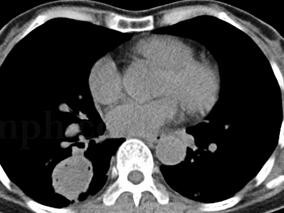

1小时条评论一、病史摘要 患者,男性,39岁,农民。因反复咯血3年,再发加重3周于2008年11月17日入院。患者自诉于3年前无明显诱因出现间断咯血,量不多,一日约10ml左右,鲜红色,伴干咳,胸痛,气促,无发热、盗汗、体重减轻等。2006年9月无明显诱因出现咯鲜血,一次约500ml。...